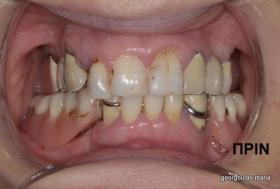

ΟΛΙΚΗ ΑΠΟΚΑΤΑΣΤΑΣΗ ΑΝΩ Κ ΚΑΤΩ ΓΝΑΘΟΥ ΜΕ ΕΜΦΥΤΕΥΜΑΤΑ, ΑΜΕΣΗ ΦΟΡΤΙΣΗ Κ ΑΝΟΙΚΤΗ ΑΝΥΨΩΣΗ ΙΓΜΟΡΕΙΟΥ

Η ασθενής αυτή είχε παλιές ακίνητες αποκαταστάσεις (γέφυρες) στην άνω γνάθο  κ μια κινητή προσθετική αποκατάσταση (μερική οδοντοστοιχία-"μασελάκι") στην κάτω γνάθο. Ήταν δυσαρεστημένη τόσο με την εμφάνιση όσο και με τη λειτουργία των δοντιών της καθώς παραπονιόταν ότι  είχαν εντονη κινητικότητα ενώ και οι προσθετικές τους εργασιές δεν ήταν σταθερές. Η πρόγνωση των δοντιών κρίθηκε φτωχή με αποτέλεσμα να μην είναι δυνατή η συμμετοχή τους σε μια νεα προσθετική αποκατάσταση με μακροχρόνια διάρκεια. Η ασθενής επιθυμούσε οι νέες αποκαταστάσεις να είναι σταθερές και ακίνητες.  Για το λόγο αυτό αποφασίστηκε η ολική αποκατάσταση της άνω κ κάτω γνάθου με ακίνητες επιεμφυτευματικές εργασίες. Στην αριστερή πλευρά της άνω γνάθου, λόγω μη επαρκούς οστού για την τοποθέτηση εμφυτευμάτων προηγήθηκε επέμβαση ανοιχτής  ανύψωσης ιγμορείου άντρου με τη χρήση πιεζοχειρουργικού μηχανήματος ώστε να δημιουργηθεί το κατάλληλο οστικό υπόστρωμα. Ακολούθησε σε επόμενο χειρουργείο η εξαγωγή των υπάρχοντων δοντιών κ η άμεση τοποθέτηση εμφυτεύματων (άμεση εμφύτευση) κ δύο μέρες μετά η τοποθέτηση προσωρινής εργασίας επί των εμφυτευμάτων (άμεση φόρτιση) με αποτέλεσμα η ασθενής να μη μείνει καθόλου χωρίς δόντια κ να είναι καλυμένη αισθητικά όσο καιρό διήρκησε η εργασία